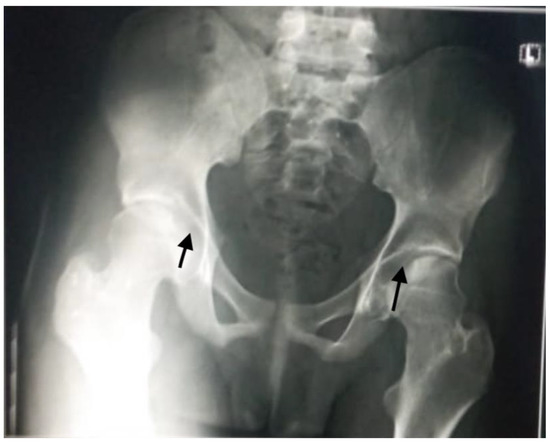

Bilateral knee arthrocentesis was performed, as well as culture of aspirate, and it all came back negative. A plain radiograph showed a mechanical non-union fracture (Salter–Harris I) of the distal end of left femur bone (Figure 1).

The Salter–Harris fracture in our patient (a type I Salter–Harris fracture) was similar to the above-mentioned report; however, in our patient, the fracture line extended through the growth plate due to a strong impact of a longitudinal force on the physis, separating the epiphysis from the metaphysis, as seen in Figure 1. Diagnosis of this type of fracture is based on clinical symptoms/physical examination of the patient with focal tenderness or edema around the growth plate, similar to slipped capital femoris epiphysis.

Figure 1. Plain X-ray of the left knee with mechanical non-union fracture.